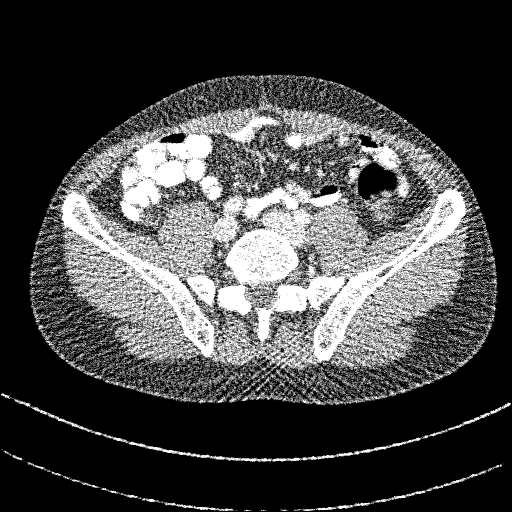

Fig. 3 visualizes sample abdominal CT images with varying quality levels from the test set. The predicted IQA scores show strong agreement with the reference scores across different noise and artifact intensities, which indicates the robustness of CAP-IQA in accurately quantifying CT image quality. The kernel density plot in Fig. 4 illustrates how prediction residuals are distributed across different IQA score groups. All curves are centered near zero, indicating balanced predictions without systematic bias toward any specific quality range. Moreover, the box plot presents the distribution of absolute prediction errors across different IQA score groups. The median errors remain low and consistent, showing that CAP-IQA performs reliably across all quality levels, with minimal variations and stability in predictions. Consistent with this interpretation, our pairwise testing using the Kruskal-Wallis H-test further confirms that there is no significant difference in performance for different IQA score groups (p-value 0.38).

4.8 Real Clinical Evaluation

We also evaluated the proposed CAP-IQA model on an in-house dataset. Fig. 8 displays sample images from the dataset. We retrospectively collected real clinical CT images from the University of Kentucky Medical Center with approval from the Institutional Review Board. A total of 91,514 image slices from 336 pediatric patients aged 2-12 years were used for testing the generalizability of CAP-IQA. Since these images have already been used for clinical diagnosis, they are expected to be of high quality (>3, as per the IQA scoring criteria in Table 1). Slice-wise IQA scores predicted by the model were averaged to obtain the overall score for each of the CT scans. The average IQA score across the 336 pediatric scans is 3.8582, with a correlation of variation of 2.1447. As seen in Fig. 9, the predicted scores are tightly grouped around the mean, with scores above the diagnostic-quality threshold of 3. The relatively high predicted scores align with expert radiologists’ assessments, indicating that the scans retain good diagnostic quality. Overall, the results demonstrate that CAP-IQA performs reliably in real-world clinical settings, and the model consistently and accurately assesses quality across diverse patient data.

![]() |

| 3.95 | 3.71 | 3.94 |

| 3.46 | 3.79 | 3.55 |